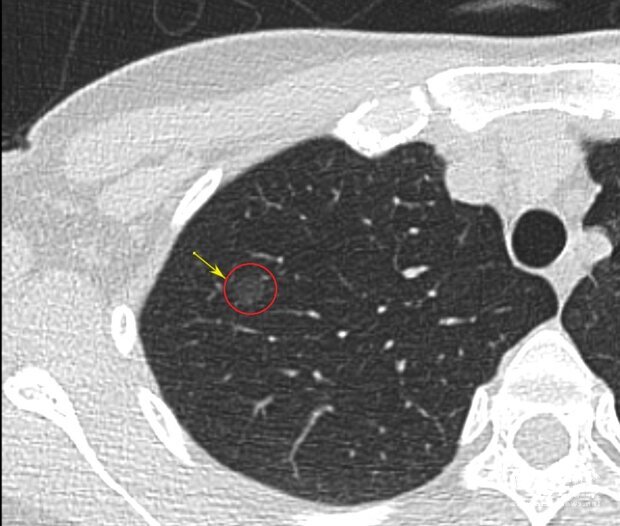

林玠虢指出,由於早期肺癌無跡象可循,以肺部毛玻璃狀病灶為例,可能不會產生任何不適症狀,但在低輻射劑量電腦斷層的檢查下,病灶會呈現出淡色顯影,可供醫師判斷是一般組織發炎或是早期肺腺癌。